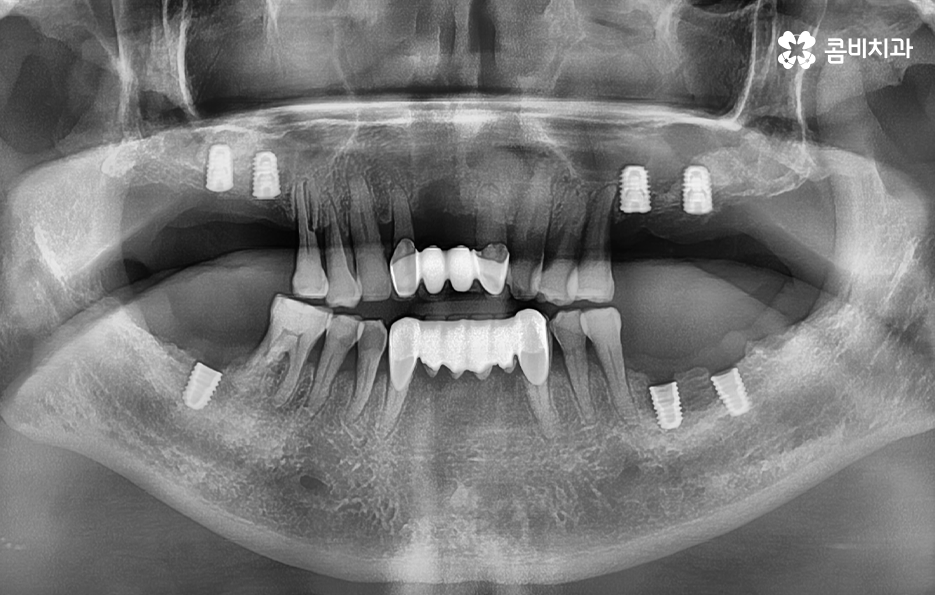

50대에 관리가 잘 안되던 치주질환은 결국 60대에 이르러 한꺼번에 여러 치아를 상실하게 되고 그에 따라 임플란트도 여러개를 식립해야 하는 사례가 많다는 점을 주목하실 필요가 있는데요

임플란트의 시술 원리는 잇몸 뼈에 식립하게 되기 때문에 충분한 골조직이 없을 때는 시술 성공률도 낮아질 뿐 아니라 장기적인 안정성도 떨어지기 때문에 잇몸 뼈가 부족하신 분들은 뼈이식을 추가적으로 해야할 수 있어요

만약 치주염으로 인해 50대임플란트 해야 하는 분들의 경우에는 뼈이식을 추가적으로 받아야 하는 경우가 있겠고 임플란트의 안정성을 확보하기 위해서는 임플란트를 고정해줄 수 있는 일정한 두께와 식립 깊이, 골질이 건강해야 하는데요

50대에는 치주염, 충치, 외상과 같은 사유로 인해 치아를 하나 둘씩 잃게 되는 사례가 많으며 치아 상실 후에 즉시 임플란트 치료를 받지 않는다면 잇몸과 턱뼈는 서서히 퇴축되고 약화되며 치열이 망가질 수 있는 우려와 교합이 제대로 물리지 않는 불균형이 나타날 수 있어요